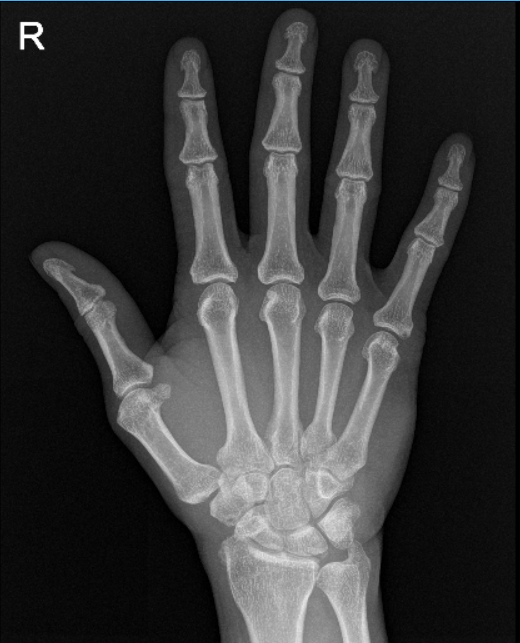

He presented X Ray of his bilateral knees, lumbar spine, and right hand from Zwanger. His Xray results showed mild osteoarthritic degenerative changes. There are no fractures. For his lumbar spine mild multilevel lumbar degenerative changes. For his right hand, normal right hand.

Right hand X-ray complete 3 or more views